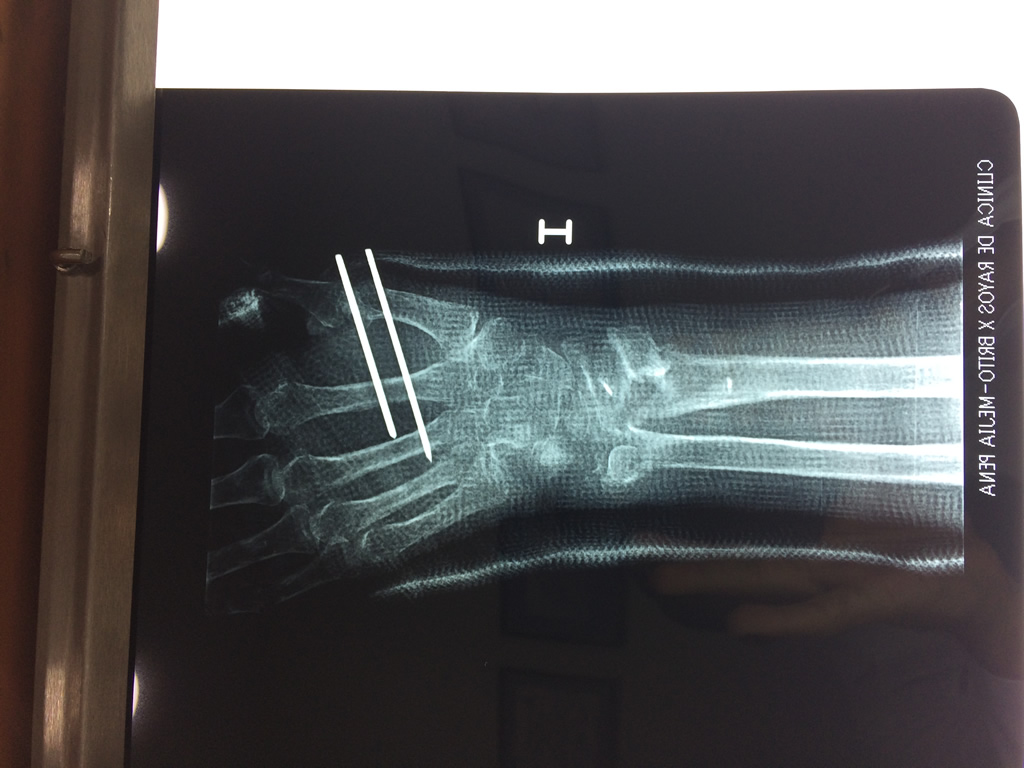

Cirugías de Muñecas

Los procedimientos más comunes en cirugía de la mano son aquellos destinados a reparar traumatismos, incluyendo lesiones de tendones, nervios, vasos sanguíneos, y articulaciones; huesos fracturados; y quemaduras, cortes, y otros daños de la piel.